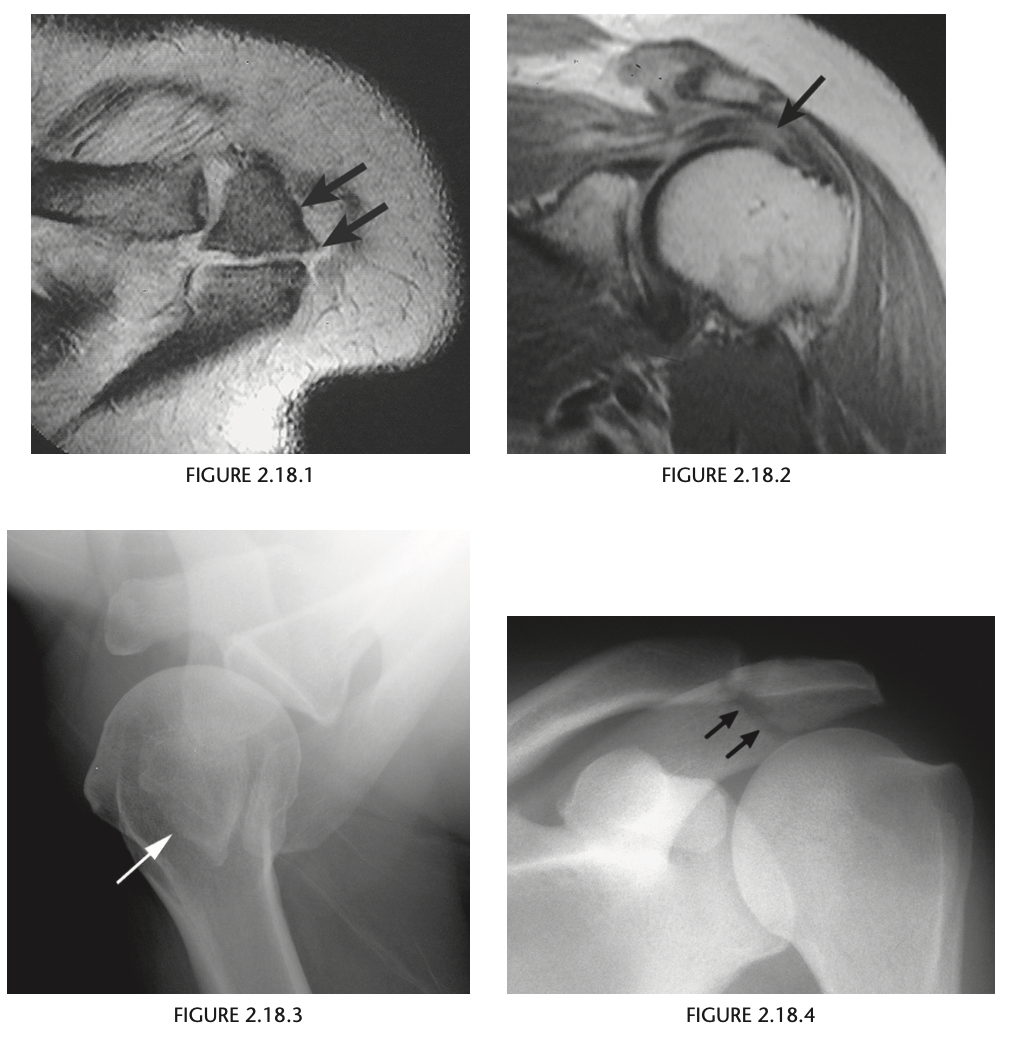

54yr old man with pain in the left shoulder.

An axial gradient-recalled echo im-

age of the left shoulder shows a well-corticated

triangular bony structure in the region of the ac-

romion (Fig. 2.18.1, arrows). Proton-density and

T2-weighted, coronal, oblique MR images of the

shoulder show hypertrophic changes that involve

the acromioclavicular joint, causing impingement

and increased signal intensity within the distal

aspect of the supraspinatus tendon, indicative of

­ tendinosis

Os Acromiale

An os acromiale is a persistent sepa-

rate ossification center for the acromion that is as-

sociated with rotator cuff tendon impingement and

tearing.

The os acromiale (Fig. 2.18.3, axillary radiograph,

arrow), with its smooth sclerotic margins, can be

easily distinguished from an acute acromial fracture

(Fig. 2.18.4, anteroposterior radiograph, arrows)

since an acute fracture has no sclerosis around the

fragment.